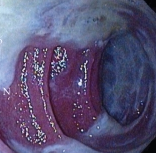

Ενδοσκοπική εικόνα της θήκης. Παρουσία μεγάλων ποσοτήτων βλέννας και ψευδομεμβρανών (Ευγενική παραχώρηση Dr. V. Penopoulos)